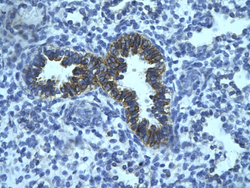

Supportive validation

- Submitted by

- Aviva Systems Biology (provider)

- Main image

- Experimental details

- Rabbit Anti-PHF16 AntibodyCatalog Number: ARP34331 Paraffin Embedded Tissue: Human bronchiole epithelium Cellular Data: Epithelial cells of renal tubuleAntibody Concentration: 4.0-8.0 ug/mlMagnification: 400X